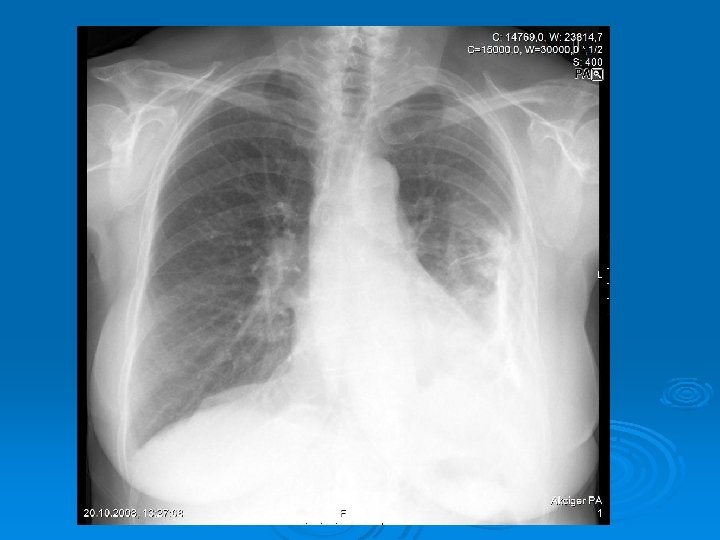

Radiology The fluid initially accumulates in the more dependent recesses of the thoracic cavity forming a Damoiseau Line Ø 200 -300 ml of pleural effusion can be detected on standard chest radiograph as blunting of the costophrenic angle Ø

Massive pleural fluid often shifts the mediastinum to the opposite side

Accumulation of the fluid between the diaphragm and the interior surface of the lung (Subpulmonic fluid): The hemidiaphragm appears to be elevated (Widening the distance between the top of the gastric bubble and the top of the left hemidiaphragm (>2 cm) and flatened Blunting of the posterior costophrenic angle on the lateral chest radiograph

Ø Smaller amounts of pleural fluid can be detected on lateral decubitus radiography as the free intrapleural fluid moves from top of the diaphragm to the dependent chest wall Pleural effusion in a lateral decubitus radiograph